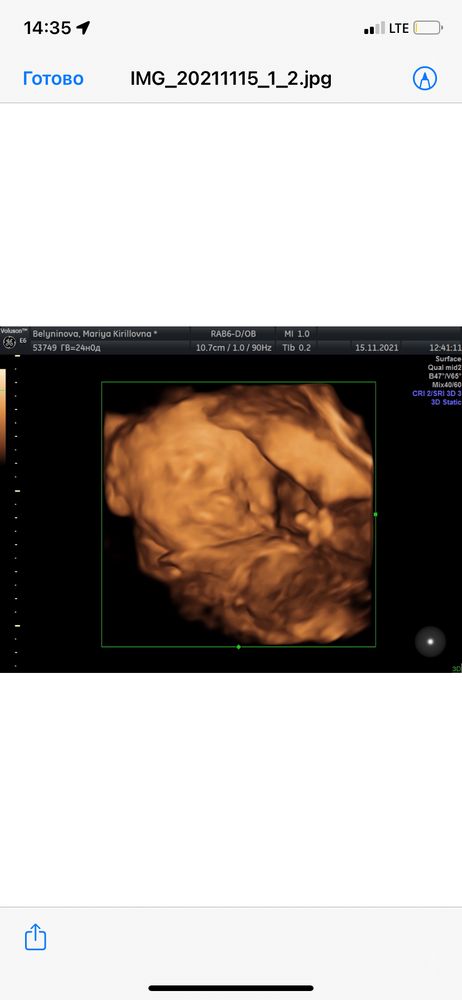

Нам хотелось фото, мы дважды делали,это круто потом ,когда малышок родился сравнивать-))